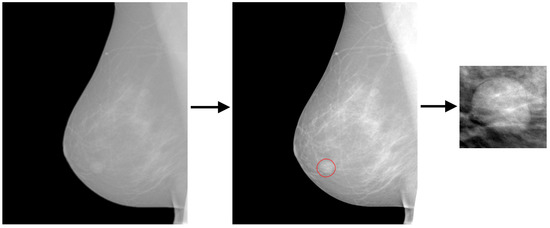

2.4. Mammography Images (Data)